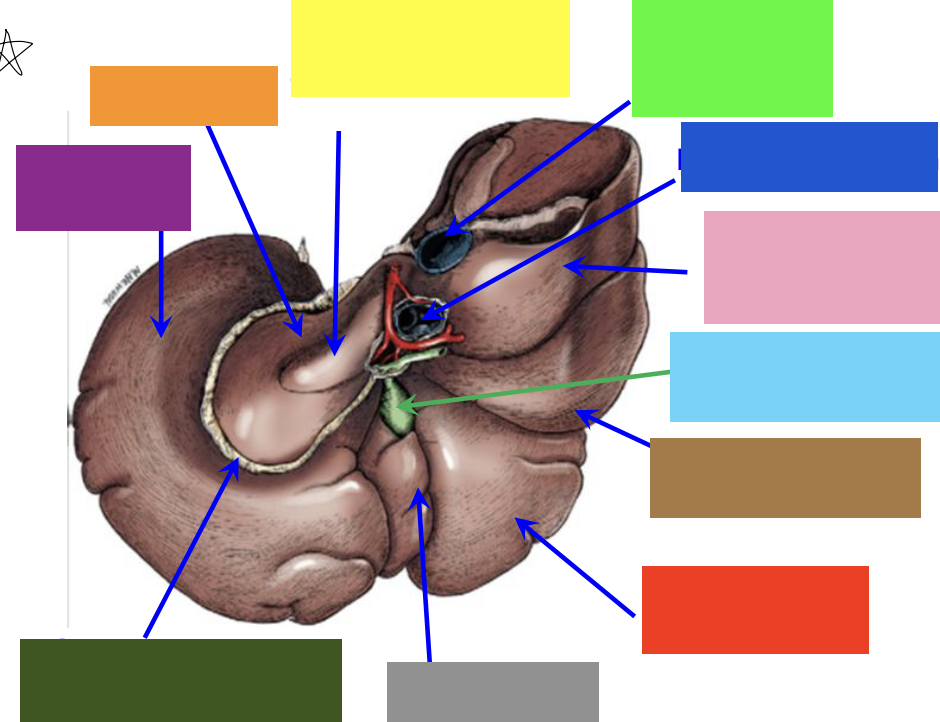

blue box

right triangular ligament

green box

right lateral lobe

purple box

coronary ligament

pink box

right medial lobe

yellow box

left medial lobe

orange box

left triangular ligament

brown box

left lateral lobe